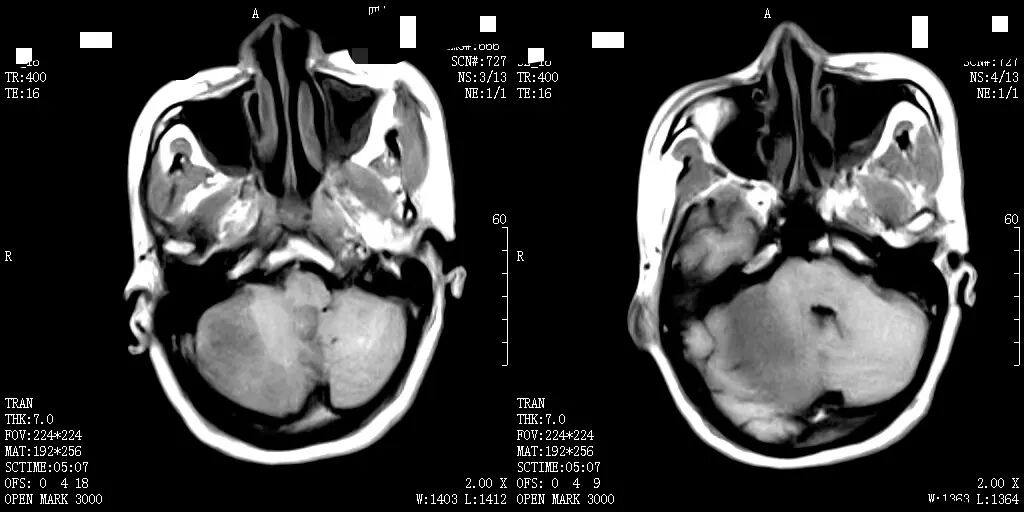

随着医学科学技术的快速发展,磁共振成像(MRI)检查作为一种非侵入性、高分辨率的成像技术,具有广泛的应用范围,已经成为临床诊断中不可或缺的工具。

何军主任以深厚的医学造诣和前瞻性视野,从MRI的基本原理讲起,深入浅出地剖析了磁共振成像的奥秘,检查方法,各类适应症,禁忌症以及最新技术应用等。从理论要点到临床应用,从经典案例到前沿技术,无一不娓娓道来,深刻阐述了MRI技术对于现代临床工作的重大意义。他强调:“MRI以其无创、多参数、高分辨率等独特优势,在中枢神经系统、心血管系统、骨关节及肌肉系统、颈部、腹部、盆腔等病变的诊断中展现出无可替代的价值,希望参与本次培训的医师们能够从中受益,学以致用。”